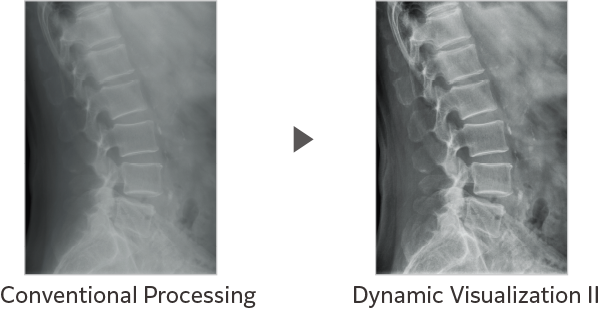

Dynamic Visualization II

Optimizes image quality using latest Exposure Data Recognizer

Advanced recognition algorithms using automatic  calculations of estimated 3D image data, identify the body part required and adjusts contrast, density and enhancement for optimised image display. (Option)

Comparison of Dynamic Visualization II vs. conventional processing images (Lumbar Spine)